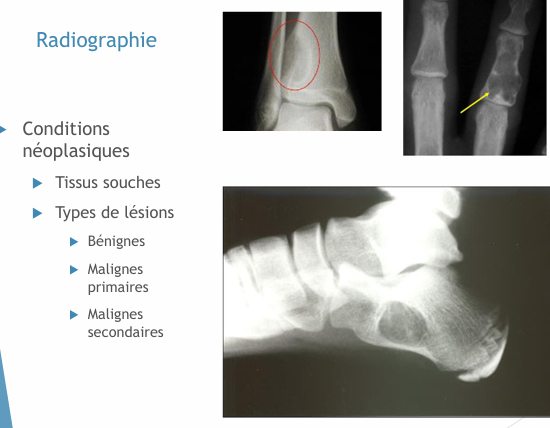

Conditions néoplasiques?

23